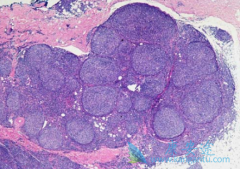

什么是淋巴瘤?常见的淋巴瘤症状有哪些?

淋巴瘤 ,是起源于淋巴造血系统的恶性肿瘤。发病率约为15/10万,近年来有增长的趋势。淋巴瘤种类繁多,症状也是多种多样。除淋巴结外,淋巴瘤还发生在胃肠道和皮肤等各种器官中,症状因部位而异。一般来说,最常见的症状是淋巴结肿大。通常在淋巴结聚集 ...